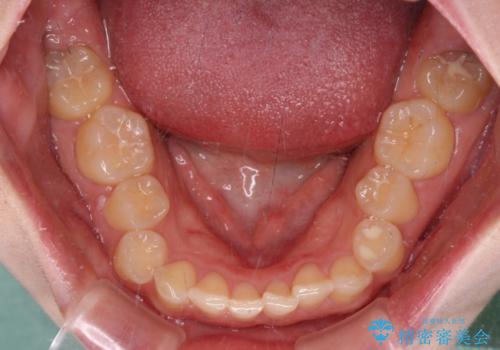

- 前歯のデコボコとディープバイトを気にして来院された患者様です。

左上前歯前方に飛び出しているため、歯列全体が前方に移動している状態でした。

短期間で確実に仕上げたいとのことで、アンカースクリューと補助装置を併用して歯列の後方移動を図り、ワイヤー装置にて矯正治療を行うこととしました。